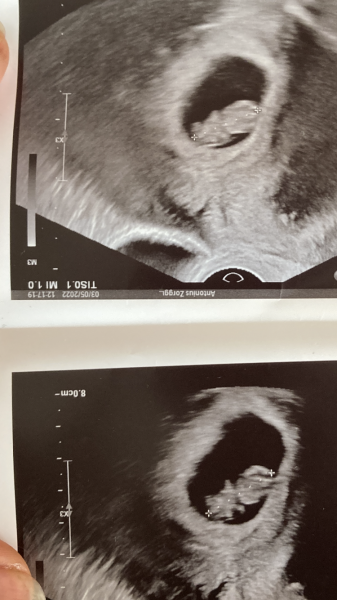

had a scan this am and all ok.measuring at 9 wks which is about right. Couldn’t get a clear pic as I have large fibroids around Going bk in 10 days. I get fairly reg scans because of uterine fibroids. Saw my baby move arms and legs! Little human now just growing.

Pinkfig · 03/05/2022 16:27

Scan went well, measuring at 6+5 like they epected, saw a flicker of a heartbeat too! She even had a look at my ovaries, I ovulated from my left ovary as I had a good sized corpus luteum. The sac looks a good size too. Very reassured.